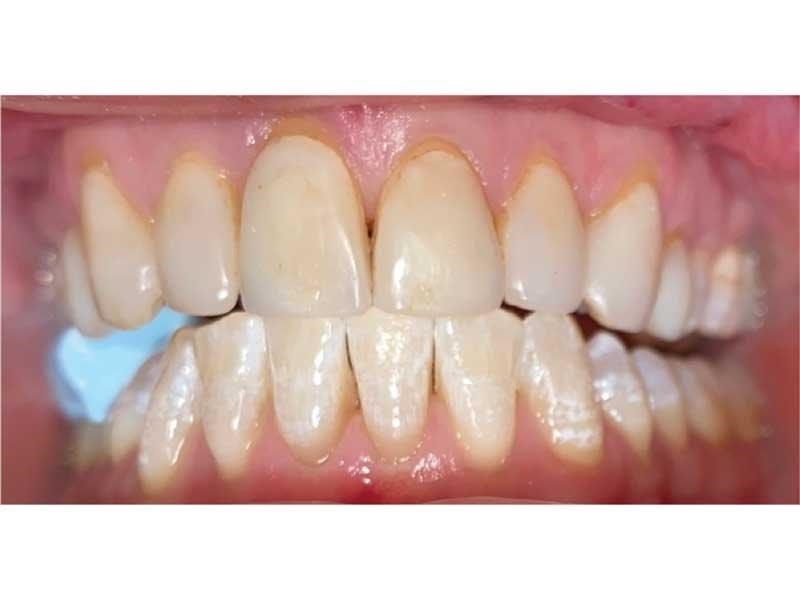

Meet Lorraine, who came into my office to “redo her bonding.” Lorraine had some upper anterior teeth done years ago with resin, which now was dull, stained and breaking down (Figs. 1–3). She had an amount of money in mind that she thought it would cost. She was very wrong.

Fig. 1

Fig. 2

Fig. 3

The big challenge: Retruded and overclosed. Lorraine looked retruded and overclosed, so I started to ask her about headaches, jaw issues and chronic pain. As we talked, she revealed that she had been in severe pain her whole life. She had all the signs and symptoms of TMD and had been to multiple doctors, pain clinics, alternative medicine practitioners, massage therapists, chiropractors, osteopaths … you name it.